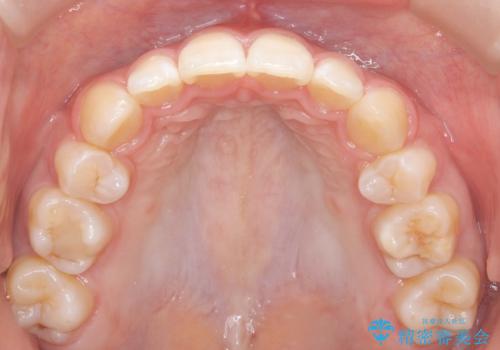

- ハーフリンガル

- 3年1ヶ月

- 出っ歯を治したいとのことで来院されました。

目立たない装置が希望とのことでハーフリンガルで治療をすることとしました。